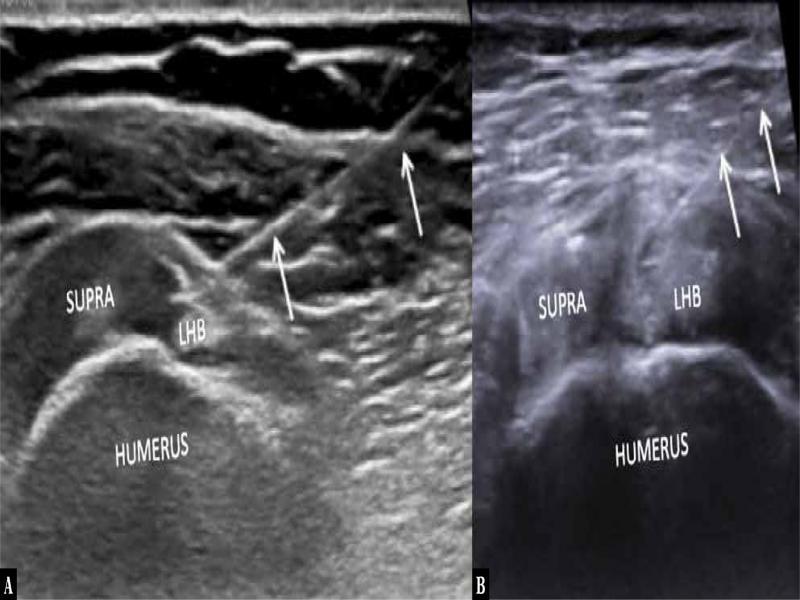

Fig. 4.

Axial ultrasound images of two patients ( A, B ) with needle tip (arrow) in the target zone via medial to lateral approach